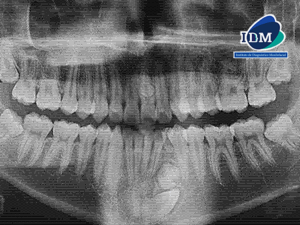

Paciente femenino de 27 años acude a IDM- Sede Jesús María con motivo de consulta para control de ortodoncia y a la evaluación de la